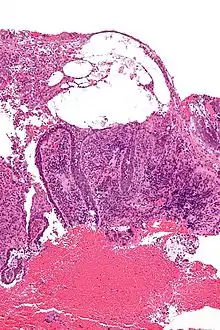

![]() صورة مجهرية للفقاع الشائع مع الصفة المميزة الشبيهة "بشاهد القبر". صورة مجهرية للفقاع الشائع مع الصفة المميزة الشبيهة "بشاهد القبر". | |

- تشكل حويصلات بشروية فوق الطبقة القاعدية

- وجود خلايا بشروية منحلة الأشواك ورشاحة التهابية من الحمضات

- علامة شواهد القبور :حيث تتباعد الخلايا القاعدية كمظهر شواهد القبور.